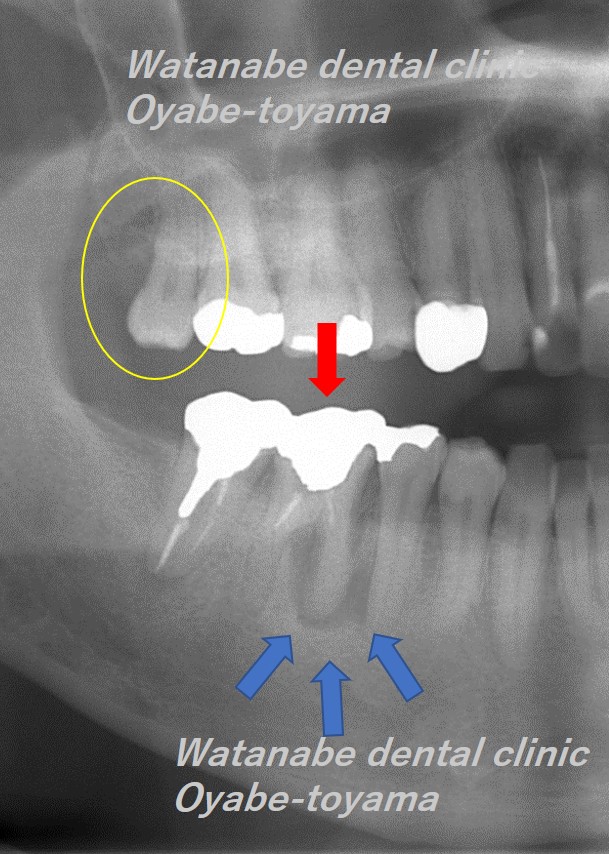

赤矢印の歯は歯根破折(根が割れている)しているため抜歯するしかありません。青矢印部分に細菌感染による大きな骨吸収が確認できます。

そこで、赤矢印の歯を抜歯して、黄色〇の親知らずを移植する計画としました。